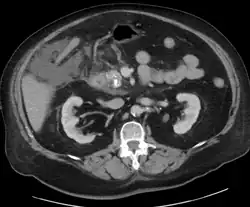

For imaging, abdominal ultrasound is convenient, simple, non-invasive, and inexpensive.[33] It is more sensitive and specific for pancreatitis from gallstones than other imaging modalities.[31] However, in 25–35% of patients the view of the pancreas can be obstructed by bowel gas making it difficult to evaluate.[30]

A contrast-enhanced CT scan is usually performed more than 48 hours after the onset of pain to evaluate for pancreatic necrosis and extrapancreatic fluid as well as predict the severity of the disease. CT scanning earlier can be falsely reassuring.[34]